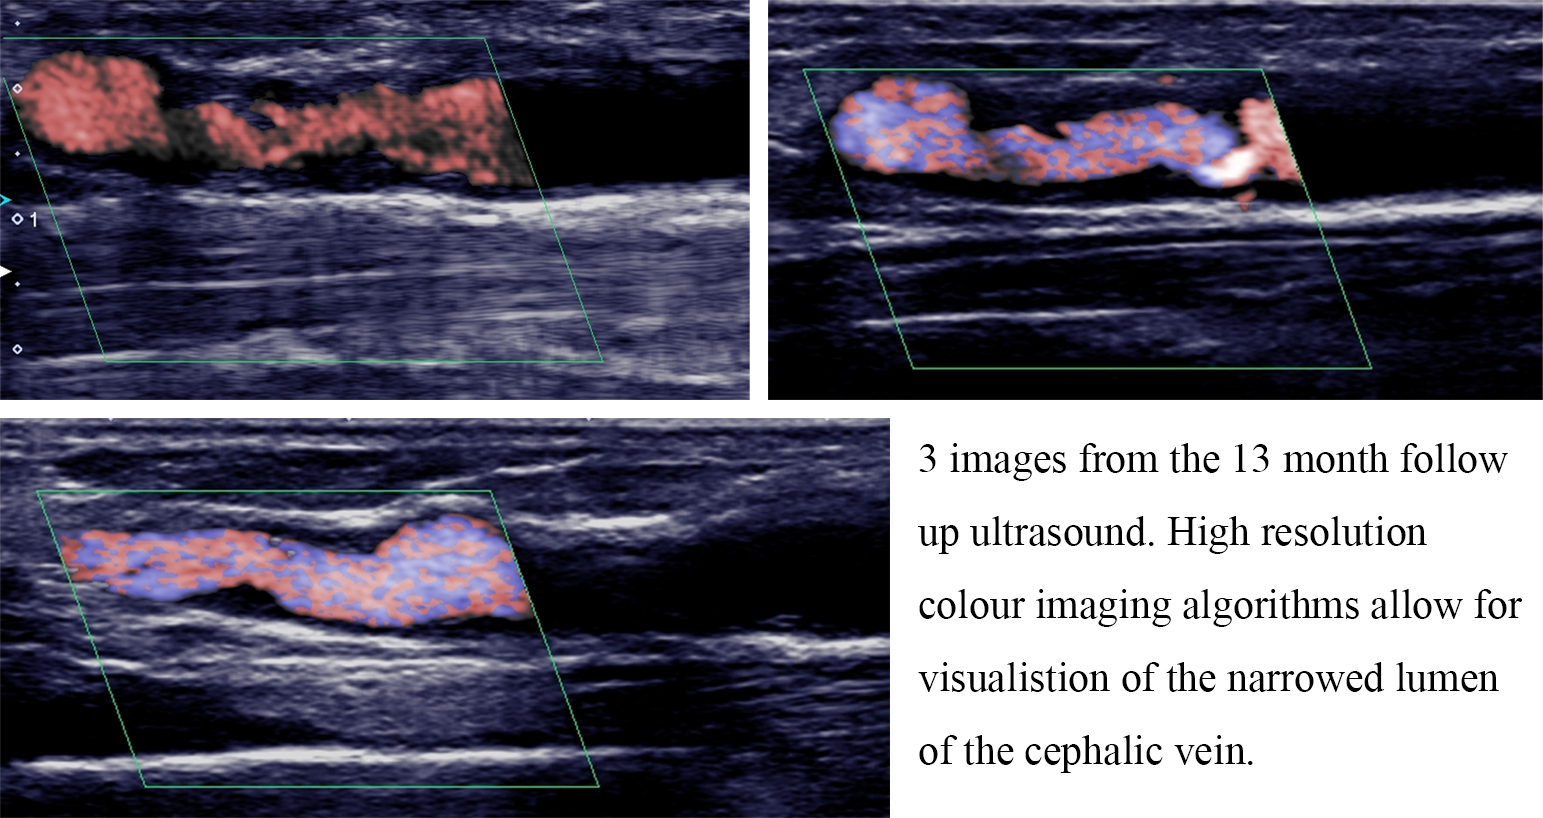

The 13-month ultrasound showed progression of NIH in the cephalic vein, resulting in a significant stenosis, extending from 22 mm above the anastomosis up to the level of the ectatic, needling zone. Flow volumes in the feeding artery had decreased from 700 mL/min to approximately 250 mL/min. High recirculation rates were reported on dialysis and the patient was referred for venoplasty of the compromised vessel segment.

Figs. 3,4 show the distribution of OSI and Holmes respectively, whilst the data presented in Table 3 shows the maximum, minimum and average values across the pre-defined regions of the upper limb anatomy (Fig. 1). Fig. 6 shows regions of NIH development, as visualized on the 13-month ultrasound.

Fig. 6.Ultrasound images showing development of neointimal hyperplasia in the efferent vein.